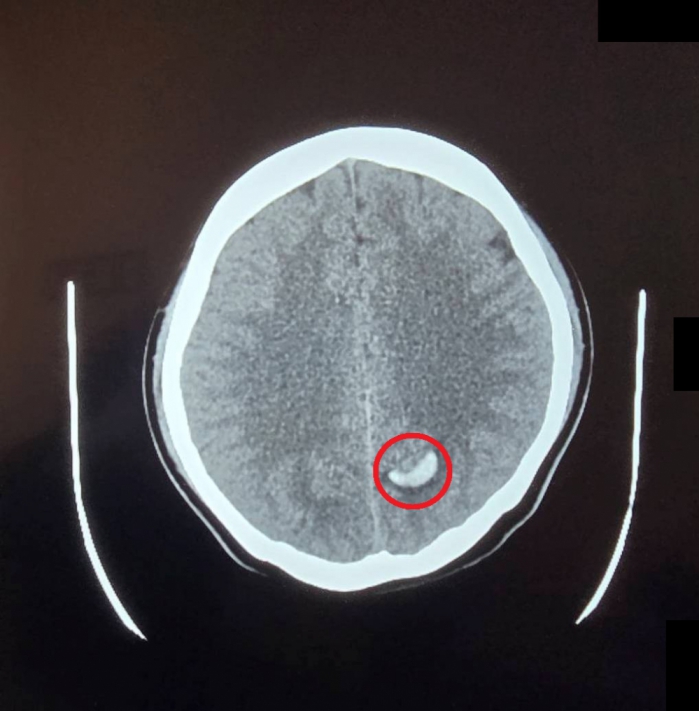

(特派員劉鳳瑩、陳明/苗栗報導)23歲的周小姐正值青春年華,日前卻在毫無預兆下感到一陣劇烈頭痛,隨即伴隨嚴重的頭暈與嘔吐感,家屬見狀趕緊將她送往大千綜合醫院急診。經腦部電腦斷層掃描,醫師赫然發現其左側腦部有出血跡象,且出血位置極其不尋常。醫療團隊隨即展開精密檢查,證實為罕見的「顱內動靜脈畸形」引發出血。所幸在神經放射科康靜維醫師及時進行微創血管內栓塞治療後,順利止住出血,病人症狀明顯改善,成功化解一場腦內危機。

大千綜合醫院神經放射科康靜維醫師指出,「顱內動靜脈畸形」是一種先天性的腦血管病變。在胚胎發育過程中,若動脈與靜脈之間缺乏微血管緩衝,導致高壓的動脈血流直接衝入脆弱的靜脈,管壁便會因長期無法負荷壓力而逐漸薄弱,最終像吹太大的氣球一樣破裂,引發腦出血。這種疾病好發於30歲左右的年輕族群,臨床表現以腦出血最為常見,但也可能出現癲癇或長期慢性頭痛等症狀。